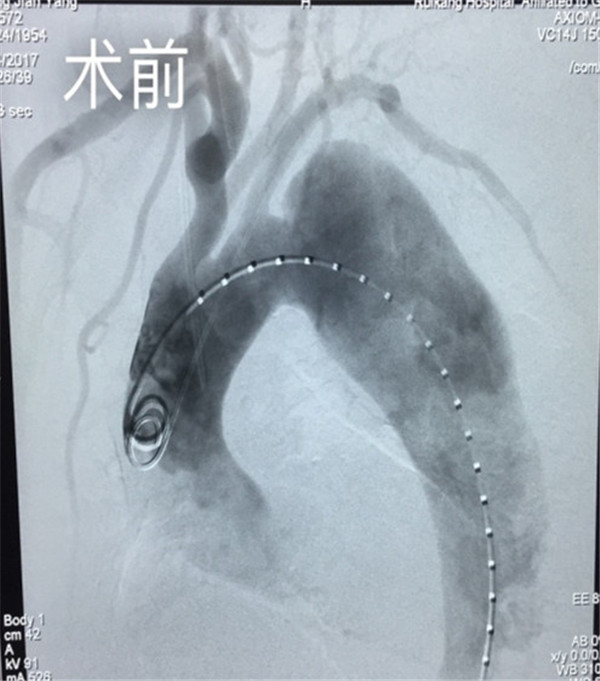

• 两代三人同患先心病 瑞康心胸外科两任主任接力救治

秦小凤(化名)是来自博白县的一位11岁小女孩,自幼她在小伙伴中便与众不同,别人发现她的口唇和指甲总是紫黑紫黑的,为了明确到底是什么问题,...

发布时间:2016-09-12 来源: